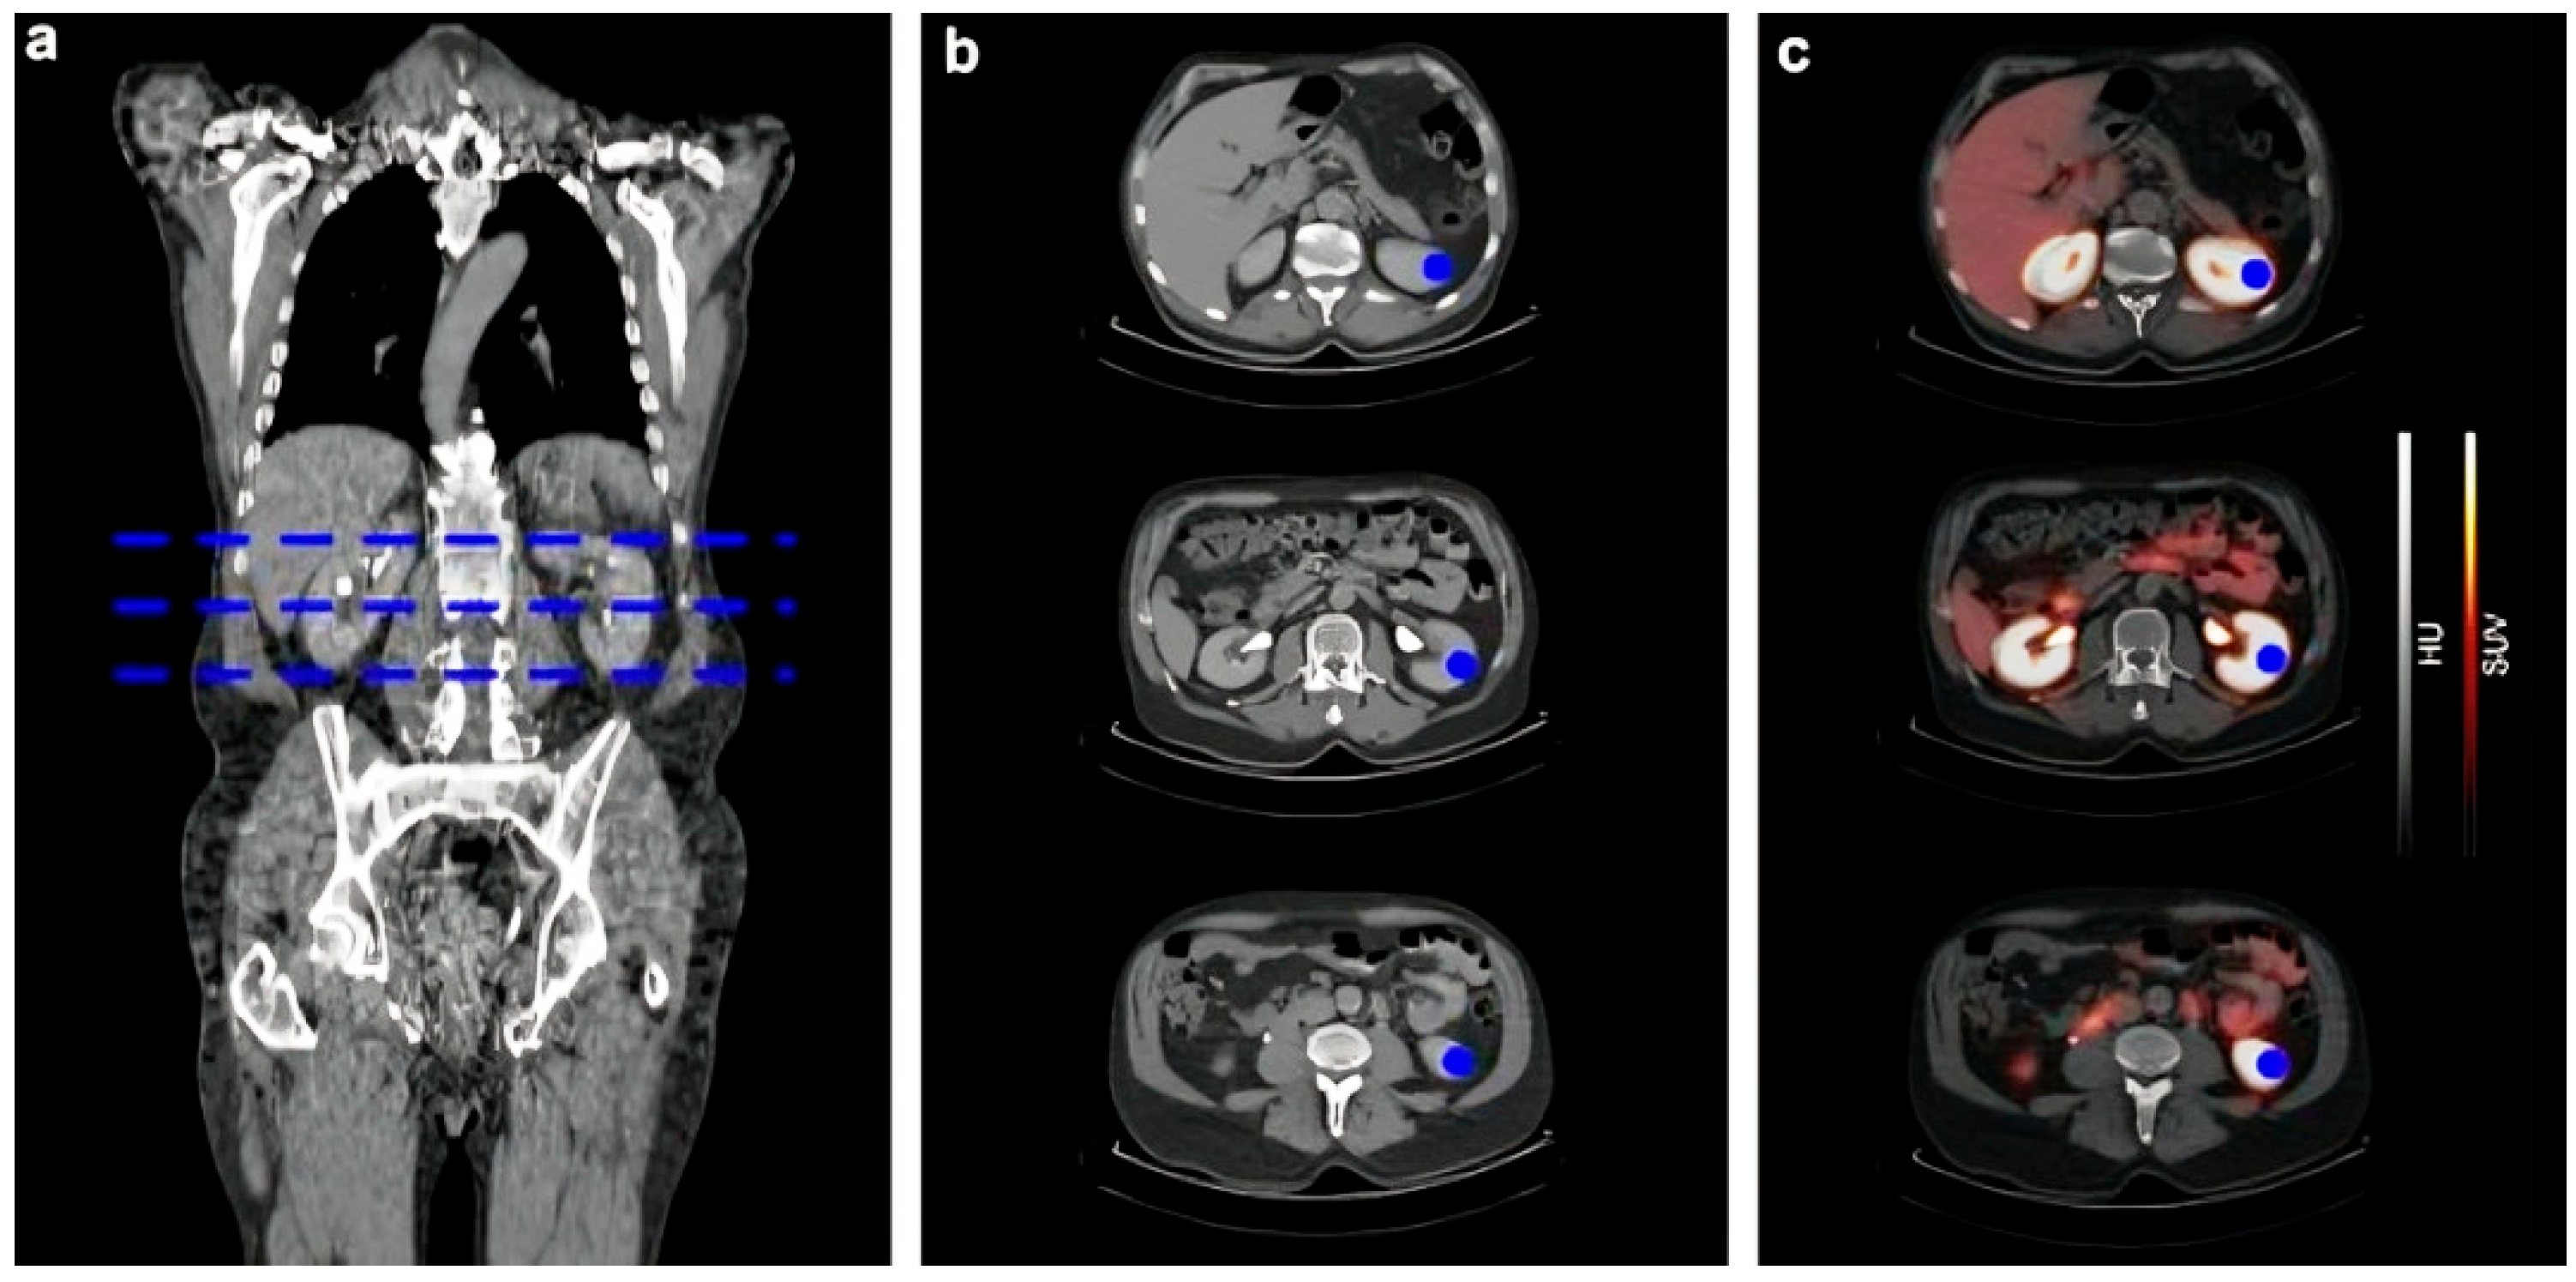

- Nishikawa, Y.; Takahashi, N.; Nishikawa, S.; Shimamoto, Y.; Nishimori, K.; Kobayashi, M.; Kimura, H.; Tsujikawa, T.; Kasuno, K.; Mori, T.; et al. Feasibility of Renal Blood Flow Measurement Using 64Cu-ATSM PET/MRI: A Quantitative PET and MRI Study. Diagnostics 2023, 13, 1685. [Google Scholar] [CrossRef] [PubMed]

| 64Cu-ATSM | Copper-64 | PET/MRI for renal blood flow quantification | Strong correlation with ASL-MRI and estimated RBF, differentiates CKD from healthy controls | First validated PET method for spatial RBF; dual modality | Small sample size, still indirect for GFR |